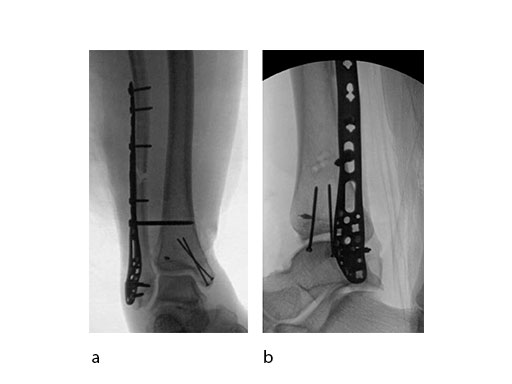

Case 2: Scaffolding fall (Case provided by Mark Lee, Sacramento, USA)

A 61-year-old laborer fell 5 meters from scaffolding. This was a closed injury with severe soft-tissue injury (Fig 67). He required three weeks of jointspanning external fixation prior to adequate resolution of edema.

Initial fixation was via a limited posteromedial exposure to buttress a posteromedial partial articular fragment (Fig 8). Following articular reduction and supplemental lateral column plate fixation via a limited anteromedial joint exposure, the VA-LCP Anteromedial Distal Tibia Plate was passed subcutaneous with subsequent percutaneous screw insertions into the plate shaft.

There was good maintenance of reduction at 5 weeks (Fig 9).